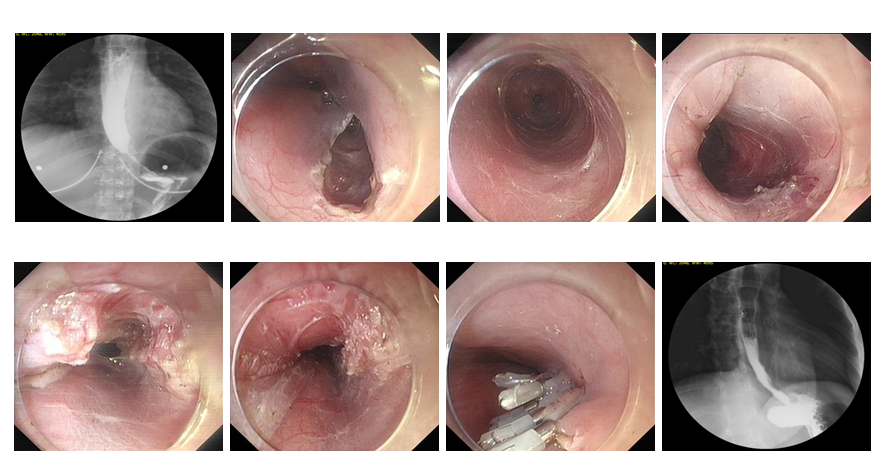

9. 消化道狭窄内镜下支架置入治疗。

10. 消化道狭窄内镜下扩张治疗。

食管胃底静脉曲张套扎、硬化术